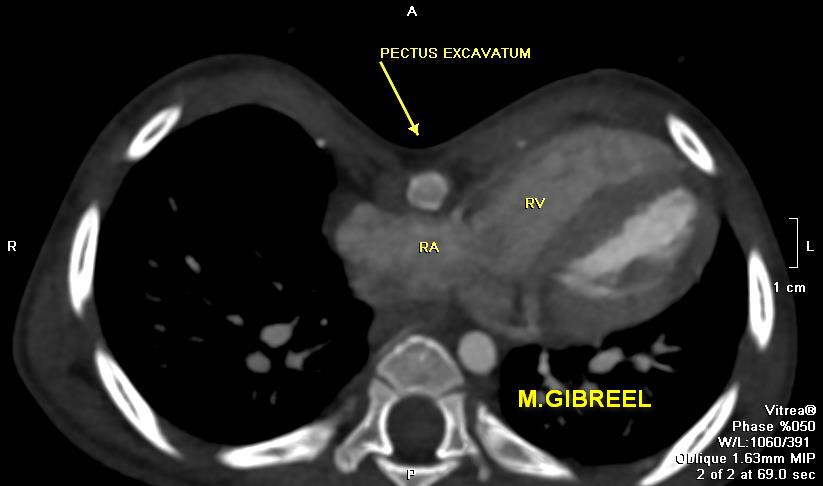

Pectus excavatum (Grade1), with longitudinal deformation of the RV & chest asymmetry,,, important measurements

MGibreel1's tweet image. Pectus excavatum (Grade1), with longitudinal deformation of the RV & chest asymmetry,,, important measurements

Pectus excavatum ,,, what to u need to be commented in your report ... From my archieve @AlkashkariWail

MGibreel1's tweet image. Pectus excavatum ,,, what to u need to be commented in your report ...

From my archieve